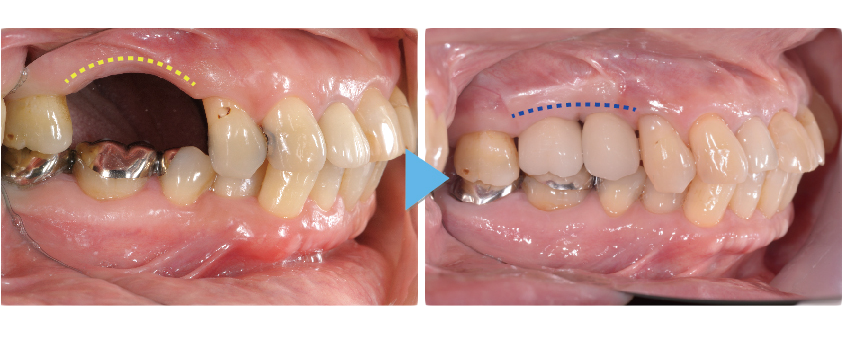

前歯のインプラント治療

前歯は周囲の骨が非常に薄いので抜歯後、時間の経過と共に歯茎は痩せて、骨も吸収して溶けてしまうことが多くあります

前歯のインプラント治療でとても重要なポイントは失った歯を回復してしっかり噛めるように機能を回復させることと、見た目が自然で人工物とわからないぐらいに綺麗にインプラント治療によって審美性を回復させることです。

しかし多くの場合、前歯の周囲の骨は非常に薄く、歯を失ったことになり顎の骨は吸収して痩せていき、それに伴って歯茎も下がってしまいます。

このままの状態でインプラント治療を行うと周りの歯と長さの違う不自然な被せ物(人工歯)になってしまい見栄えが悪く清掃性もよくありません。

そのため前歯のインプラント治療では、より正確な位置にインプラントを埋入することが求められ、インプラント周りの歯茎も自然な仕上がりになるようにインプラント周囲組織の骨や歯茎も回復をしてあげる必要があります。

コンピューターガイデッドインプラント治療 + 歯科用顕微鏡を用いたマイクロサージェリー 審美的に良好な結果が得られています

当院では、コンピューターガイデッド インプラント治療で正確な位置にインプラント手術を行い、そして前歯などの審美領域では顕微鏡を使用したマイクロサージェリー(顕微鏡下手術)を行うことで傷跡の目立ちにくい自然な仕上がりのインプラント治療を行っています。